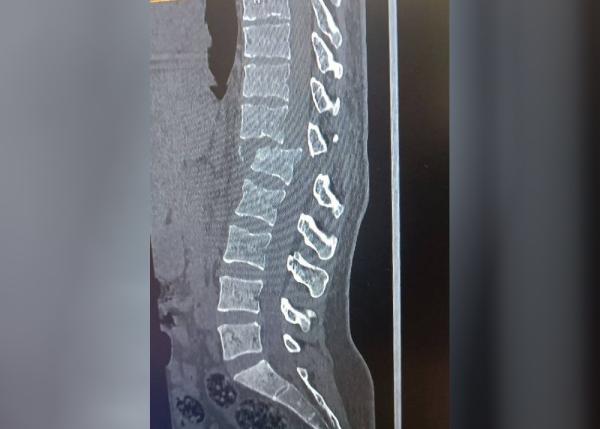

Утром 14 августа на своем «Дамасе» он сбил супругу, когда она шла по обочине дороги. Женщина получила тяжелые травмы: перелом позвоночника, повреждение нервных окончаний и паралич нижней части тела. Сейчас она находится в больнице, ей требуется дорогостоящая операция в Ташкенте, на которую у родственников нет денег. Муж, виновный в ее инвалидности, отказывается помогать с лечением.